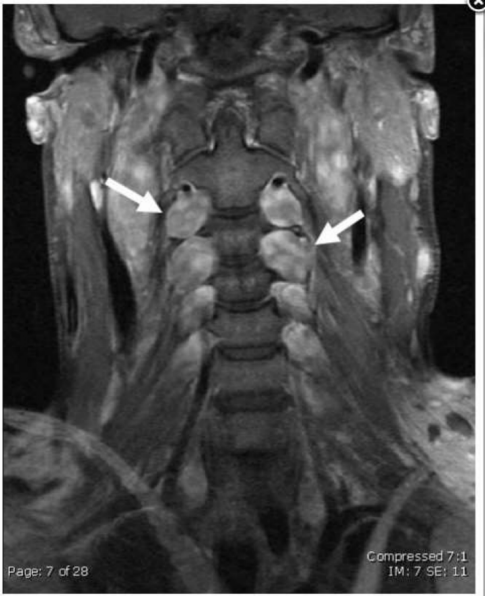

A 14-year-old female presents with progressive difficulty writing. An MRI (figure) shows multiple nodular areas

running along the cervical nerve roots and brachial plexus. Examination of her eyes also shows iris harmartomas.

What is the most likely diagnosis?

Neurofibromatosis-1